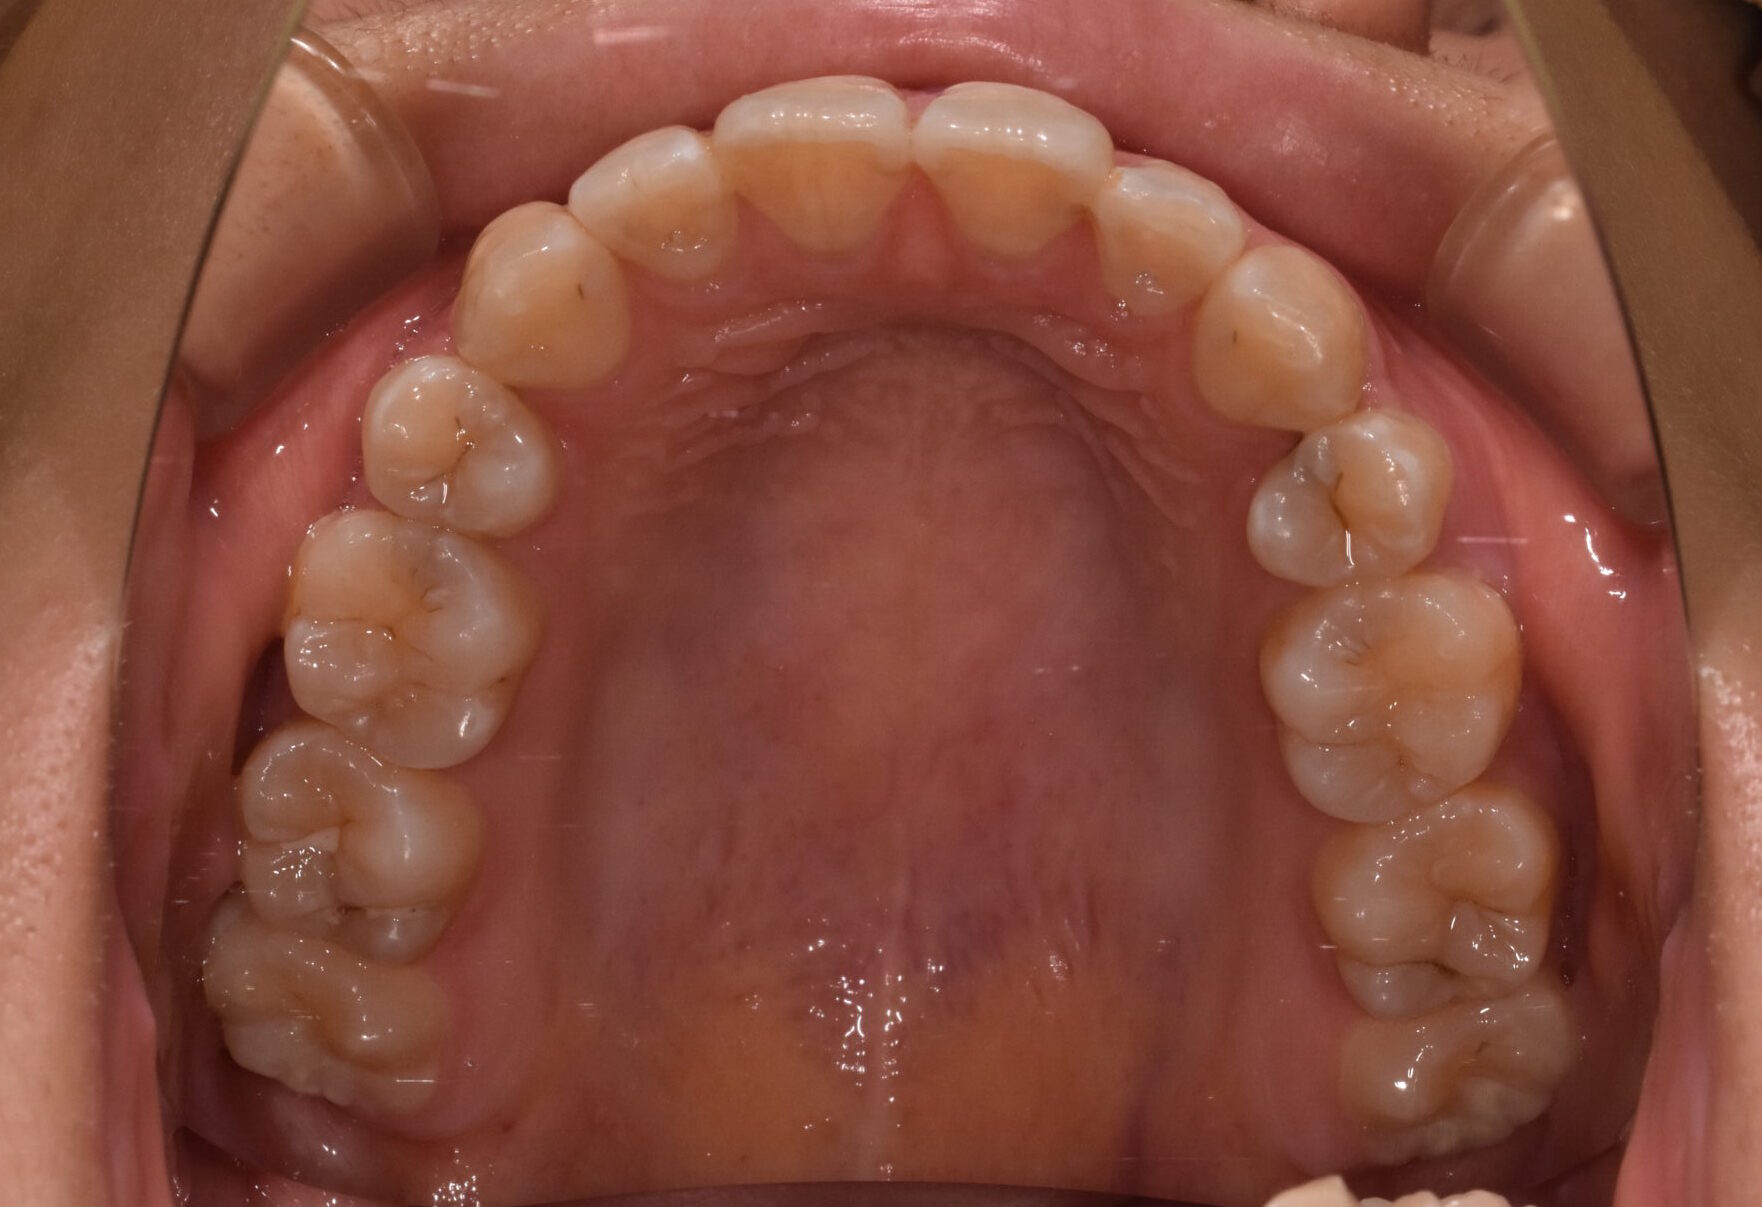

開咬 17歳 女性

治療前

骨格:開咬傾向(前歯が噛みにくいタイプ)

歯並び:前歯が噛み合わない(開咬)+前歯の突出傾向

上下左右の第1小臼歯(4番)を抜歯し、マウスピース型矯正装置を用いて歯並びとかみ合わせの改善を行いました

・抜歯によりスペースを確保し、前歯の位置と角度をコントロール

・奥歯の高さを調整し、前歯がしっかり噛むように改善